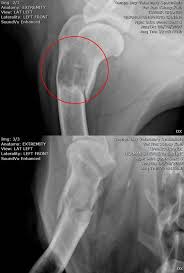

Signs Of Bone Cancer In Dogs Leg - Dr Wiltzius Shares Canine Bone Cancer Diagnosis Staging And What To Expect - Osteosarcoma is a word derived from osteo, meaning bone, and sarcoma, meaning cancer.. They can include swelling, lameness, and joint or bone pain. Veterinarians often use the phrase away from the elbows & toward the knees to remember the anatomically predisposed sites, including: Dog bone cancer warning signs sometimes bone cancer makes a sudden appearance as a lump in the leg, or in worst case scenario, as a pathologic fracture. When the tumor first appears, the site usually looks slightly swollen. Or a dramatic, sudden fracture.

Other types of bone cancer include chondrosarcoma, fibrosarcoma, and hemangiosarcoma. Osteosarcoma is a common dog cancer in large breeds, and it most often affects the long bones of the legs. Most dogs will show signs of swelling and soreness in limbs close to joints. Usually, osteosarcoma develops in the long bones of the front legs, though the rear legs, jaw, face. Symptoms of bone cancer in dogs: If you decide to proceed with amputation, you will admit your pet into the hospital either the day before or the morning of surgery. Canine bone cancer may be part of the diagnosis. Sometimes a biopsy is performed by taking a small piece of bone and testing it. They can include swelling, lameness, and joint or bone pain. The early signs of bone cancer in dogs can difficult for pet parents to recognize since symptoms tend to be subtle. Symptoms and types many signs of bone cancer are subtle. (most dogs with this kind of cancer do not survive beyond a year with amputation alone. Canine bone cancer symptoms osteosarcoma tumors typically form in a dog's long bones, or growth bones, and are found frequently below the elbow or near the knee or shoulder.

Dog bone cancer warning signs sometimes bone cancer makes a sudden appearance as a lump in the leg, or in worst case scenario, as a pathologic fracture. As the tumor continues to grow, the bone containing the tumor will expand. Washington ( circa) — osteosarcoma (osa) is one of the most common forms of bone cancer seen in veterinary patients. Osteosarcoma is a type of bone cancer. Other types of bone cancer include chondrosarcoma, fibrosarcoma, and hemangiosarcoma. Since we can't ask our dogs how they are feeling each day, it's important to understand the signs of a sick dog. How to help our mastiff with bone cancer. While tumors usually occur in the long bones of the limbs, osteosarcoma can affect any bone. It's the cancer of the bones. Osteosarcoma is the most common bone cancer in dogs. Symptoms of bone cancer in dogs: Osteosarcoma (osa) at the top of the list, osteosarcoma is the most prevalent type of bone cancer in dogs. Sometimes a biopsy is performed by taking a small piece of bone and testing it.

Osteosarcoma Bone Cancer In Dogs from www.aspcapetinsurance.com Sadly, the outlook for a dog with an osteosarcoma. While tumors usually occur in the long bones of the limbs, osteosarcoma can affect any bone. This bone cancer grows very quickly and frequently spreads to other areas of the body, especially lymph nodes, lungs and other bones. The total length of anesthesia time is usually three to four hours. Lameness caused by osteosarcoma is typically mild at the onset, but then progresses over time. Osteosarcomas are painful tumours that often first appear as hot, solid, tender swellings. Osteosarcoma is a type of bone cancer. Sometimes a biopsy is performed by taking a small piece of bone and testing it.

Tumor growth destroys healthy tissue, causing the bone to swell. Leg amputation surgery in pets. Osteosarcoma (osa) at the top of the list, osteosarcoma is the most prevalent type of bone cancer in dogs. He is walking comfortably without limping and is able to run around a bit in the yard. This is a major operation, and the serious complications rate is up to 5%, with a fatality rate of less than 1%. Responsible for 85% of all malignancies of a dog's. Most dogs will show signs of swelling and soreness in limbs close to joints. Mast cell tumors are cancer of these cells, and they. By j weatherford (marietta ga) we discovered yesterday that max has bone cancer in his left rear leg. Dog bone cancer warning signs sometimes bone cancer makes a sudden appearance as a lump in the leg, or in worst case scenario, as a pathologic fracture. The total length of anesthesia time is usually three to four hours. If however, your dog appears to be in pain, or is holding a leg completely off the ground and refuses to put weight on it, an immediate vet appointment is crucial. While tumors usually occur in the long bones of the limbs, osteosarcoma can affect any bone.